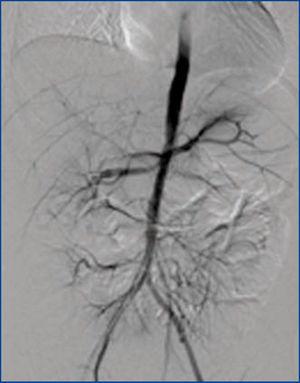

Se realiza nueva arteriografía, que reportó aorta abdominal irregular con adelgazamiento distal progresivo, oclusión de la anastomosis arterial del autotrasplante y progresión de la estenosis arterial renal derecha (figura 2); se decidió hacer angioplastia primaria renal derecha, la cual no fue exitosa por persistencia de la estenosis. Por el difícil control de las cifras de presión arterial se realiza muestreo venoso selectivo de las venas renales para medición de renina, encontrando una diferencia de 10:1 en las concentraciones del riñón autotrasplantado contra el riñón derecho. Esto confirmó la sospecha de hipertensión renovascular originada en el riñón autotrasplantado. No fue posible realizar embolización de la arteria renal autotrasplantada por riesgo de necrosis extensa, ya que se encontraron ramas parasíticas que aportaban flujo al riñón autotrasplantado y a los músculos intrínsecos de la pelvis. Se decidió hacer nefrectomía del autotrasplante izquierdo. La evolución fue satisfactoria con mejor control de las cifras de presión arterial, por lo cual la paciente fue dada de alta.

Figura 2. Arteriografía abdominal